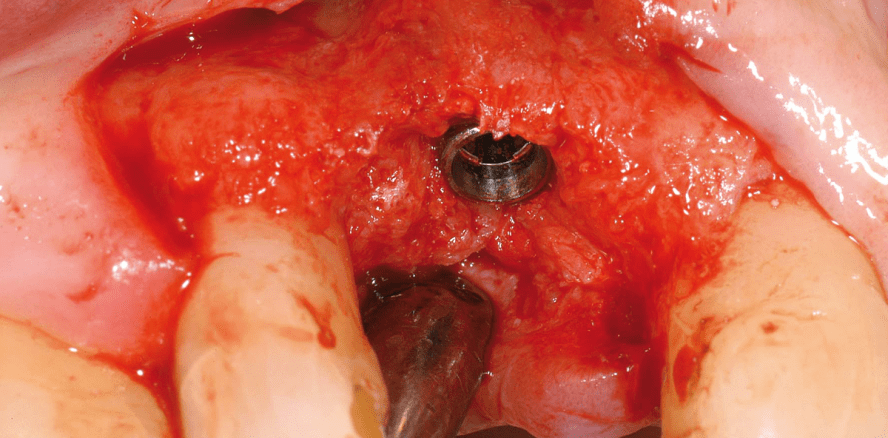

Die Implantation erfolgte zweieinhalb Monate nach der Extraktion. Es zeigte sich ein gesundes Weichgewebe mit ausreichend keratinisierter Gingiva (Abb. 13). Der ehemalige Extraktionsdefekt war vollständig knöchern konsolidiert ohne Zeichen eines krestalen Volumenverlustes (Abb. 14). Die knöcherne Struktur des Implantatbettes zeigte sich trotz der kurzen Zeit nach Augmentation fast vollständig konsolidiert, die primärstabile Implantatinsertion konnte ohne weitere augmentativen Maßnahmen in das ehemals augmentierte Areal erfolgen (Abb. 15–17).

Die bei Extraktion fehlende bukkale Knochenstruktur konnte fast vollständig wiederhergestellt werden, sodass das Implantat in ein breites vitales Knochenbett inseriert werden konnte (Abb. 29–30).